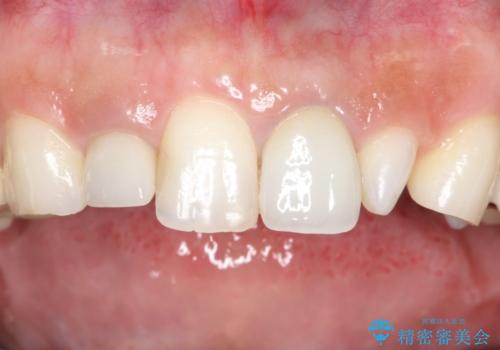

インプラント埋入手術は1回で全て行い、2ヶ月後にはセラミック治療で、審美回復と機能回復をしました。

来院回数が少なく、しっかり食事もできるとの事で非常に喜んで頂けました。